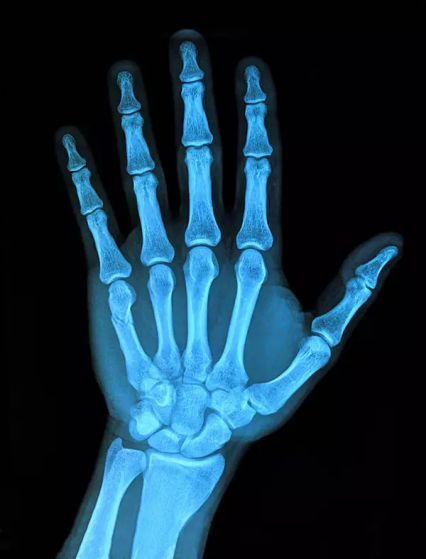

1、外傷骨頭——粗看X光攝影、細(xì)看CT

當(dāng)遇到各種外傷,如果懷疑傷到了骨頭,優(yōu)先選擇X光攝影,檢查結(jié)果快速易得。若要進(jìn)一步觀察,可以選擇CT觀察細(xì)節(jié),甚至磁共振成像觀察隱匿損傷或軟組織損傷。